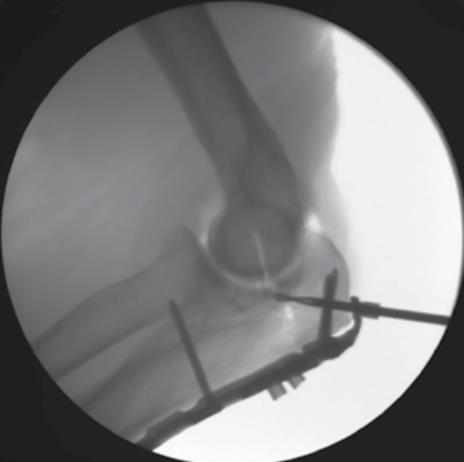

• Fluoroscopic Confirmation

• repeat steps past two steps for the remaining olecranon screw hole using a 3.5mm Multi-Thread Locking Screw

• confirm proper plate positioning, fracture reduction and screw lengths using fluoroscopic imaging

• fluoroscopic imaging is helpful during this step

• using fluoroscopic imaging, confirm that proper reduction has been maintained and that all screws are of proper length and fully engaged to the plate

• confirm that all PDGs have been removed.

• confirm that the new trajectory avoids contact with the articular surfaces and other screw trajectories using fluoroscopy